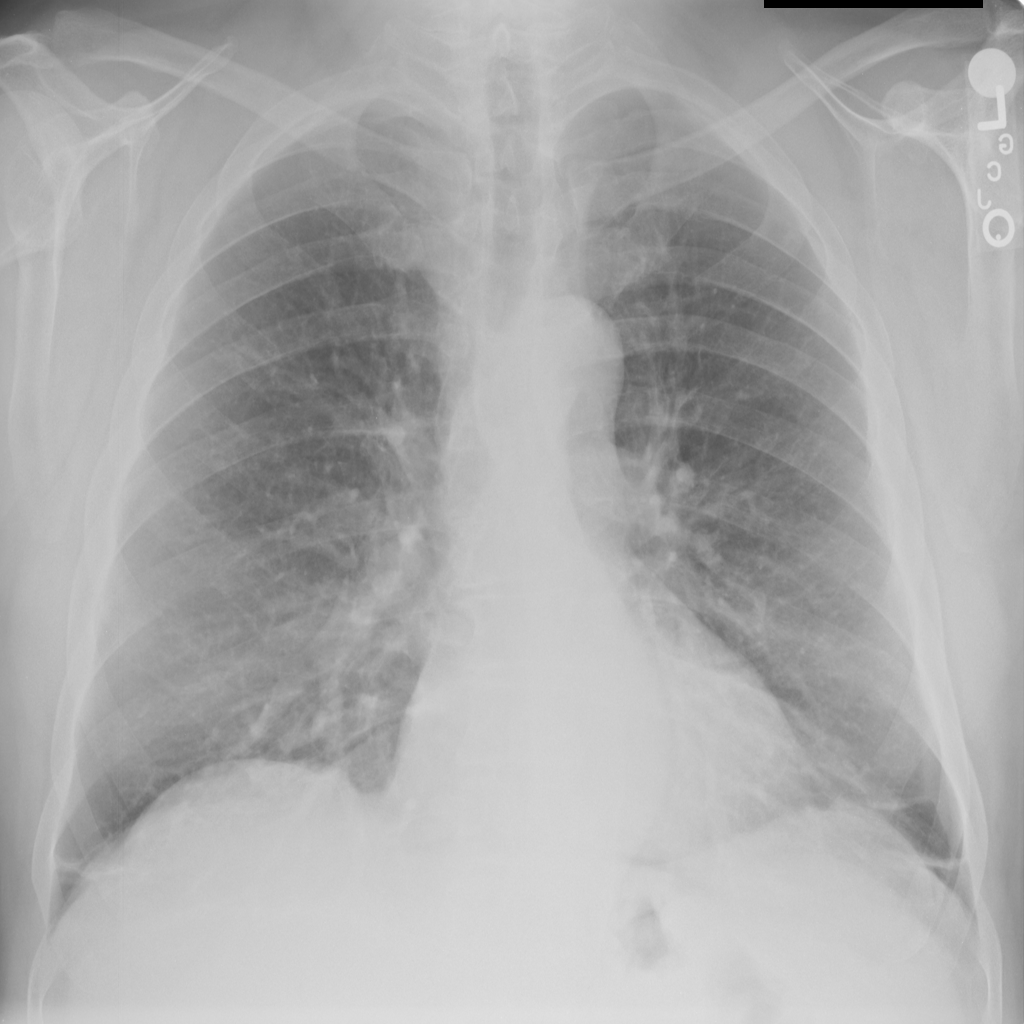

PAT-86C8 · IMG-006Atelectasis

PAT-86C8 · IMG-006

PA